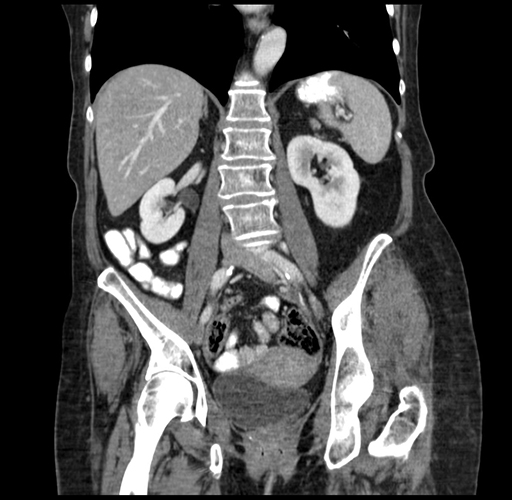

Pre-Chemo: Coronal Venous